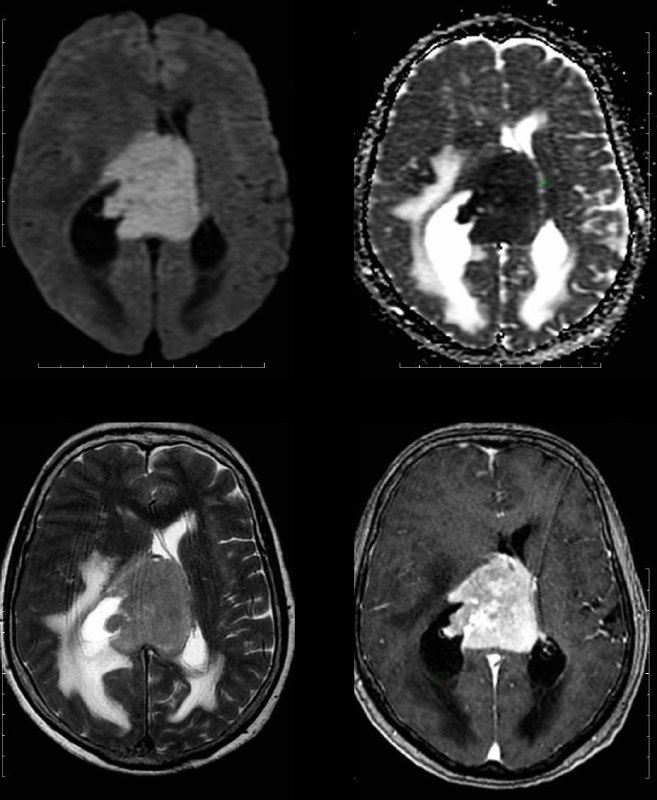

Глиобластома.

Разница в две недели.

Отек стал меньше из-за стероидов.

Но растет быстро, сволочь…